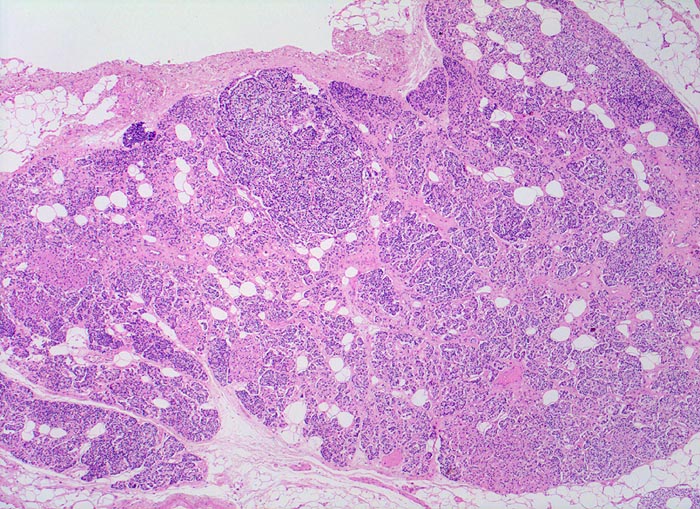

Morphologisch besteht bei sHPT eine Hauptzellhyperplasie. Makroskopisch findet sich eine meist ungleich ausgebildete Vergrösserung aller Nebenschilddrüsen. Die Grösse der Drüsen entspricht der Schwere und der Dauer des Stimulus. Die im früheren Stadium gefundene diffuse Hyperplasie mit Ersatz des Stromas und der Fettzellen durch chronisch stimulierte Hauptzellen (> 558) (> 559) geht im späteren Stadium in eine noduläre Hyperplasie („Pseudoadenome“) über (> 2358). Die regulierte Anpassung der Nebenschilddrüsen kann in eine Autonomie übergehen (tHPT) (> 3704). Morphologisch besteht in diesem Fall eine unregelmässige noduläre Hyperplasie. Gelegentlich entwickelt sich beim tHPT ein dominanter Knoten, der morphologisch nicht von einem Adenom bei pHPT unterscheidbar ist.

• Knotige vergrösserte Nebenschilddrüse. Abgrenzung der einzelnen Knoten durch breite Fibrosebänder.

• Hyperplasie lipidarmer Hauptzellen.

• Areale mit oxyphilen Zellen.

• Verminderter Fettgehalt (<<35%). Für normale Nebenschilddrüsen gilt: